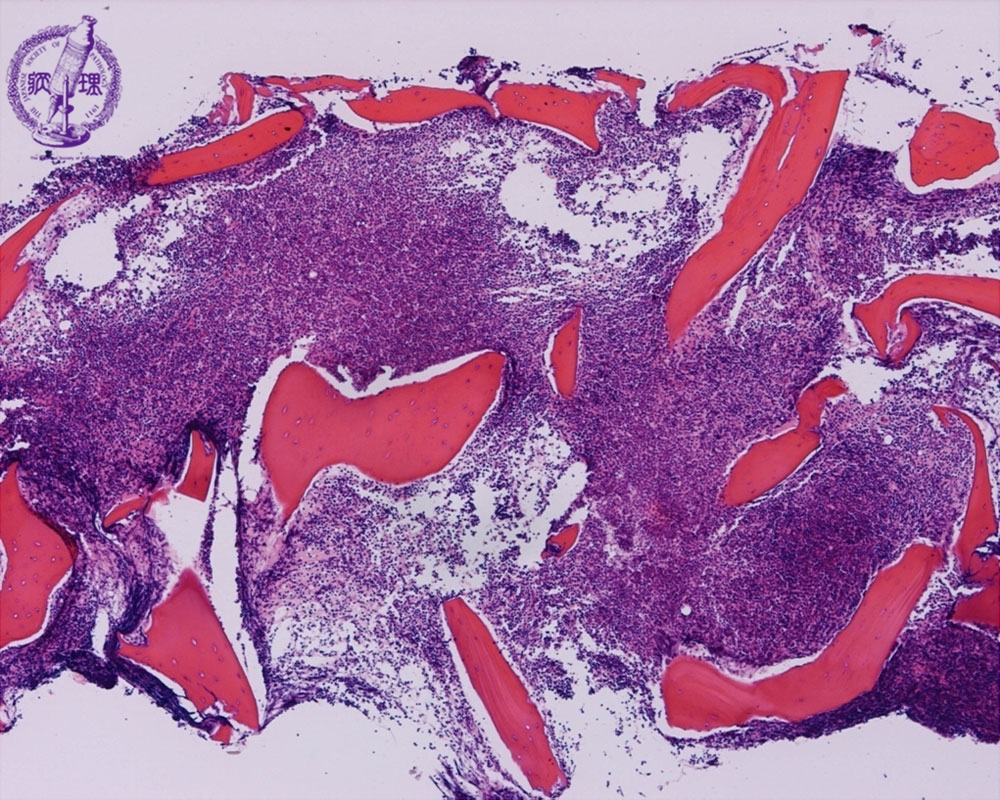

Microscopic image (H&E low power view): The marrow is hypercellular with a proliferation of atypical lymphoid cells. A N/C ratio is high in these cells. This is the picture of ALL (L1 by FAB classification).